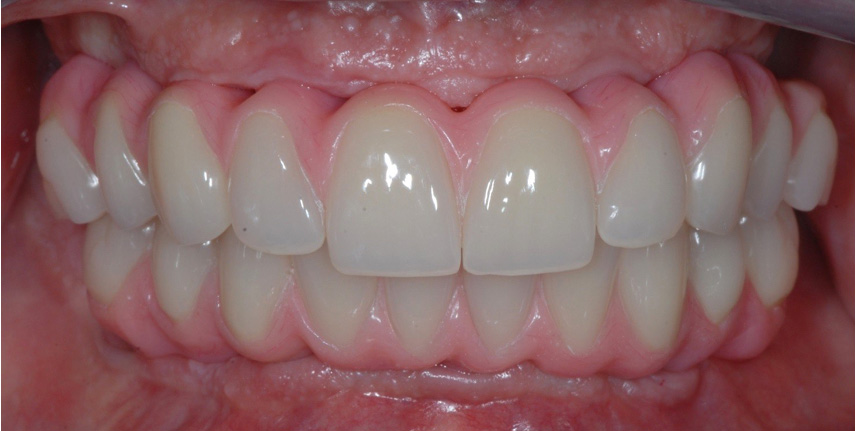

Gli impianti hanno il compito di sostituire uno o più denti mancanti, fino ad un’edentulia completa, e di servire da sostegno per una protesi ad essi ancorata.

Le tecniche che utilizziamo sono sviluppate per rispondere al meglio alle vostre esigenze: invasività della chirurgia ridotta al minimo, nessun taglio della gengiva, chirurgia software guidata e carico immediato sono solo alcuni degli accorgimenti studiati per ridurre al minimo i disagi legati alla chirurgia.